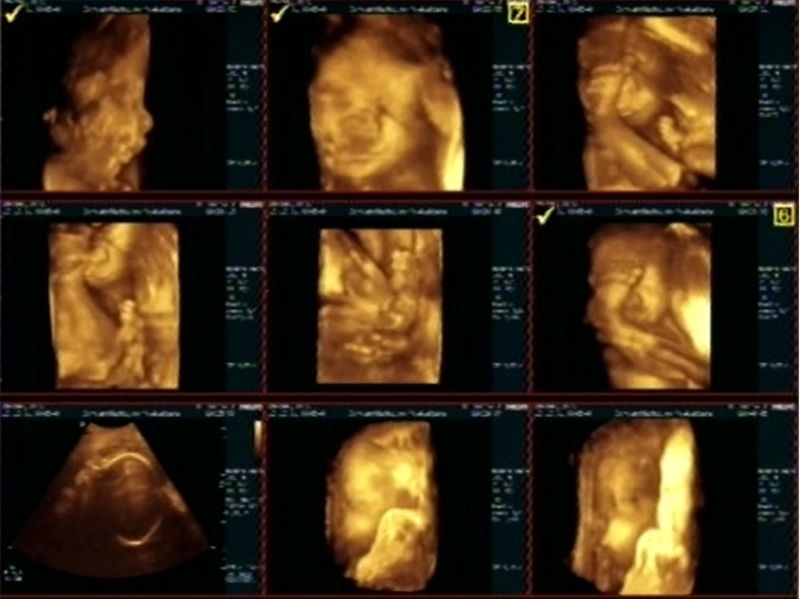

En dan woensdag avond de echo... Helemaal geweldig!

Baby is alleen een beetje eigenwijs enne erruch lenig XD Handjes voor t kruis en voetjes voor t gezichtje.. Onze ik was dus ook ipv aan het duimen aan het tenen, hihi

Hier wat printscreens van de DVD

Kijk ik duim niet maar ik teen:

Mijn profiel en minineusje die ik graag tegen de BM wand aan druk als ik niet mijn voetje er tussen heb :P (Ow ja, de kleine kriebelt me dus niet met de handjes zoals ik dacht maar t zijn dus de voetjes die de kleine bij, naast, boven en onder t hoofdje houd).

Boos kijken:

Lachen:

Enne ja, Geen facepalm op de traditionele manier maareuh... Mat de voet dus :p Gewoon omdat het kan XD

Drinken:

En nog wat overzichtjes: